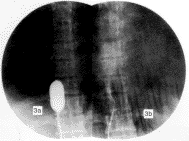

3.3 治疗效果的判定 球囊扩张手术效果一般根据手术前后静脉压的变化以及造影结果判定,但单凭静脉压降低难以判断狭窄是否完全扩开,故笔者采取在扩张中观察到的直观影像来判断扩张效果和作为终止手术的指征:当扩张开始时,由于膜对球囊的束缚,球囊形成“8”字形(见封三图2),继续加压,“8”字凹陷消失,反复几次后,如果从电视监视屏上观察到从加压开始,球囊即由小到大呈均匀性扩张,没有出现中间缩窄环或局限性压痕,就可以考虑狭窄已基本扩开(见封图3a),可将造影剂抽出少许,使球囊略缩小,上下移动导管,观察有无阻力,如无明显阻力,则进一步证实狭窄已完全扩开,则可中止扩张,抽空球囊,在原狭窄下方造影,可见造影剂被快速的血流冲击迅速散开呈云雾状进入右房(见封三图3b),术前锥形狭窄影像消失,如更换导管行快速加压造影效果更为满意。

图3a 扩张完成,膜状狭窄消失

图3b 在狭窄下方造影,造影剂呈云雾状迅速进入右房,原锥状狭窄影像(见1a)消失